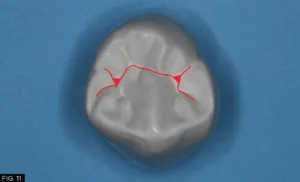

As with any dental restoration, it is paramount that if it is to function properly and to be undetectable, the natural tooth morphology must be adhered to. There are essentially 8 common occlusal anatomy guidelines in posterior human tooth shape. (Refer to Figure 18 on the bottom of the page) This is only a guideline as variations in human occlusal tooth anatomy can be expected in nature. For this patient, using anatomical guidelines, tooth #28 (#44) occlusal theme is depicted in Fig 11.

However, a cross section of the occlusal theme of tooth #28 (#44) commonly has two planes connecting both buccal/lingual cusp tips into the central groove and both mesial/distal fossae as indicated with the red and yellow lines which must be taken into consideration. (FIG.12)

The red and yellow lines highlight the two-plane occlusal form of tooth #28 (#44), connecting the buccal and lingual cusp tips to the central groove and mesial/distal fossae.

The proper occlusal anatomy of any posterior tooth can be created with a simple flame shaped fine diamond bur (Komet® FG8888) which will allow you to carve the two planes that make up the triangular ridges while following the occlusal pattern of a particular posterior tooth as seen with this patient. (FIG.13) The tip of the bur is used to develop the fossa and steeper planes (red) and the remaining tooth structure will guide your less steep plane (yellow) development.